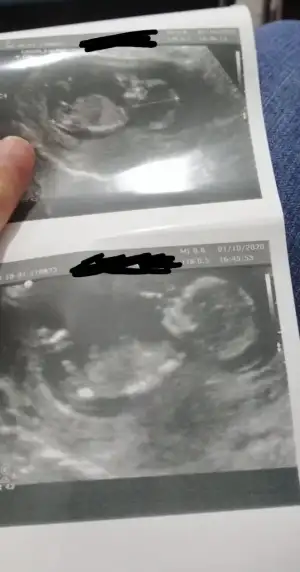

İkizlerimin 11. ve 13.hafta ultrasonları. Cinsiyetlerini anlayabiliyor musunuz?Canım.baska yok mu nubu çok karışıktipi kız gibi öncekine ne demiştim